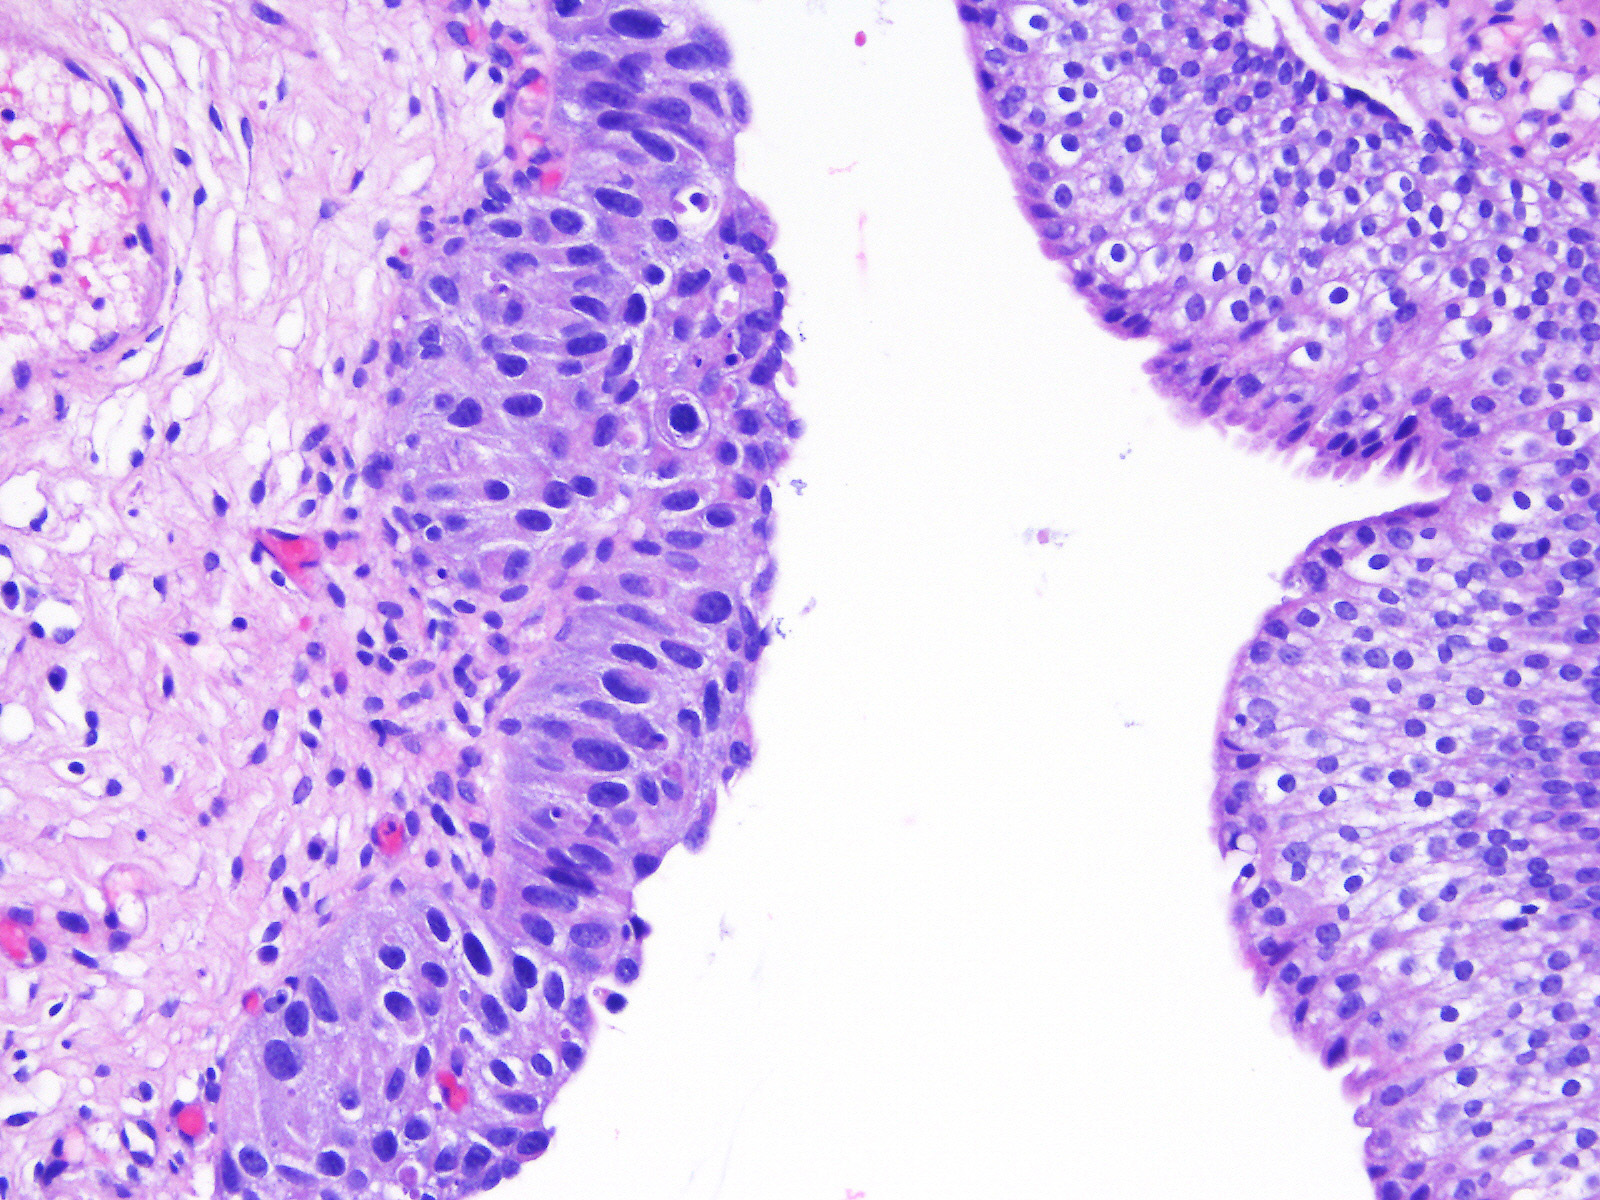

Consensus grade: Carcinoma in situ (CIS)

A 60-year-old man had atypical urothelial cells on urine cytology. Cystoscopy revealed several lesions in the bladder that were biopsied. He had a history of bladder urothelial CIS treated with intravesical BCG therapy and 3-month follow-up cystoscopies and cytologies were unremarkable.